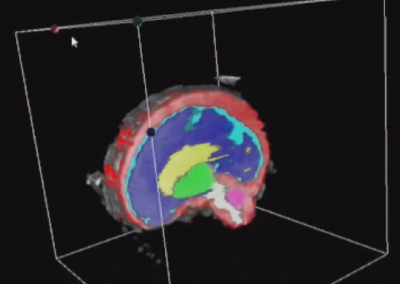

L’Université Paris Cité franchit une nouvelle étape dans le domaine de l’imagerie médicale anténatale avec l’acquisition d’un système d’Imagerie par Résonance Magnétique (IRM) 1,5T ARTIST™ de GE HealthCare. Cet équipement de pointe renforce les capacités de la Plateforme LUMIERE à l’hôpital Necker-Enfants malades, plateforme intégrée de soins, de recherche clinique et d’enseignement en imagerie médicale de la femme enceinte, du fœtus et du placenta.

L’acquisition de cette nouvelle IRM s’inscrit dans le cadre du protocole de recherche « LUMIERE SUR LE FETUS », dont les objectifs sont d’améliorer la prise en charge des pathologies anténatales, d’affiner leur pronostic et de contribuer à la réduction de la morbidité et de la mortalité à court, moyen et long terme. Cette acquisition a été rendue possible grâce au don exceptionnel de la Fondation LUMIERE d’un montant de 250k euros ainsi qu’au soutien de l’Université Paris Cité à hauteur de 670k euros.

L’inclusion de ces patientes, depuis leur accueil jusqu’à la réalisation des examens d’imagerie, puis l’analyse des images et l’interprétation des résultats par des équipes expertes, enrichit une base de données structurée, unique au monde, au service de la recherche et de l’innovation en imagerie anténatale et en médecine fœtale.

La Plateforme LUMIERE accueille chaque année plusieurs jeunes chercheurs (masters, doctorants et post-doctorants). Leurs travaux de recherche visent, à terme, à améliorer le diagnostic et le pronostic des pathologies anténatales, afin de mieux anticiper et optimiser la prise en charge des nouveau-nés. Ces travaux ont déjà mené à des communications et des publications scientifiques dans des revues à comité de lecture.

En soutenant des vocations scientifiques et en accompagnant celles et ceux qui construisent la recherche de demain, la Plateforme LUMIERE contribue activement à l’enrichissement des connaissances sur le développement fœtal et placentaire.